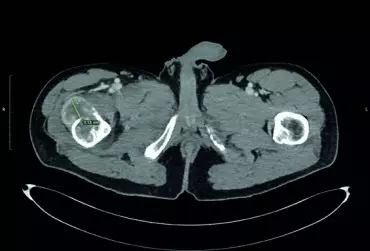

Nowe technologie w Ortopedii: zastosowanie okularów mieszanej rzeczywistości (MR) podczas operacji resekcji przerzutu raka jasnokomórkowego nerki do kości udowej

Przerzuty raka jasnokomórkowego nerki do kości ze złamaniem patologicznym stanowią poważny problem leczniczy. Pojedyncze ogniska należy traktować jak guz pierwotny i resekować w całości. Przerzut raka jasnokomórkowego nerki cechuje się patologicznym unaczynieniem, które wymaga przedoperacyjnej embolizacji. Zastosowanie okularów MR umożliwia realistyczne planowanie operacji, ułatwia resekcję guza, resekcję kości i wpływa na zmniejszenie czasu operacji, utratę krwi i zmniejszenie ryzyka infekcji.